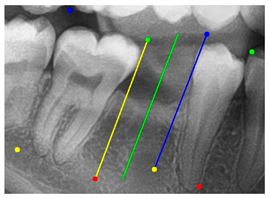

The angle bisector of the two auxiliary lines was then calculated using the angle bisector formula shown in (8), where (, , ) and (, , ) represent the coefficients of the two lines. The resulting internal angle bisector defines the preliminary implant pathway orientation derived by this framework. This bisector represents the most stable implant pathway orientation direction, ensuring that the implant avoids adjacent teeth and critical anatomical structures while maximizing bone–implant contact area. Such orientation enhances osseointegration stability and prevents complications from improper angulation, such as malocclusion or uneven stress distribution. The visualization of this process and the algorithmic design are presented in Figure 8. Finally, the auxiliary pathway generated by the algorithm was compared and overlapped with the implant pathway orientation annotated by dentists on the images to evaluate the predictive capability and accuracy of the model. The overlap results serve as a basis for further model optimization and provide valuable reference information for clinical application.

Figure 8.

Auxiliary lines are derived from adjacent teeth, the blue and yellow line is the result of implant pathway orientation visualization algorithm, and the green is the best implant pathway orientation.

3.3. Comparison with Clinical Ground Truth and AI-Assisted Framework

This subsection presents a comparison between the dentist-defined clinical gold standard and the predictions generated by our AI-assisted framework to evaluate the reliability of implant pathway orientation. The result is shown in Table 10, the preserved DPR validation set was used for verification, and the AI-assisted framework results were overlaid onto the original DPR images to provide a clear visualization. The AI-assisted framework pathways (green lines) were highly consistent with the dentists’ ground-truth annotations (black lines). Quantitatively, the mean squared error (MSE) between the predicted implant direction and the dentists’ planned results was only 1.537° across multiple test images. This minimal deviation validates the proposed system’s technical feasibility. It highlights its clinical potential to provide accurate and stable guidance for implant placement, thereby reducing the risk of misalignment and supporting efficient preoperative orientation.